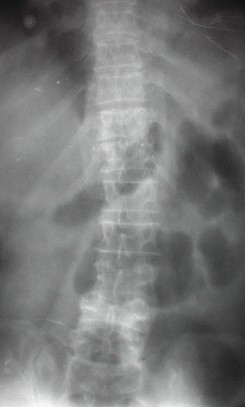

Case 1

68 y. old female

Diabetic

Discitis D 10 - 11

First stage anterior debridement and strut grafting.

Second stage posterior instrumentation and fusion.

Her neurology improved from Frankle B to D